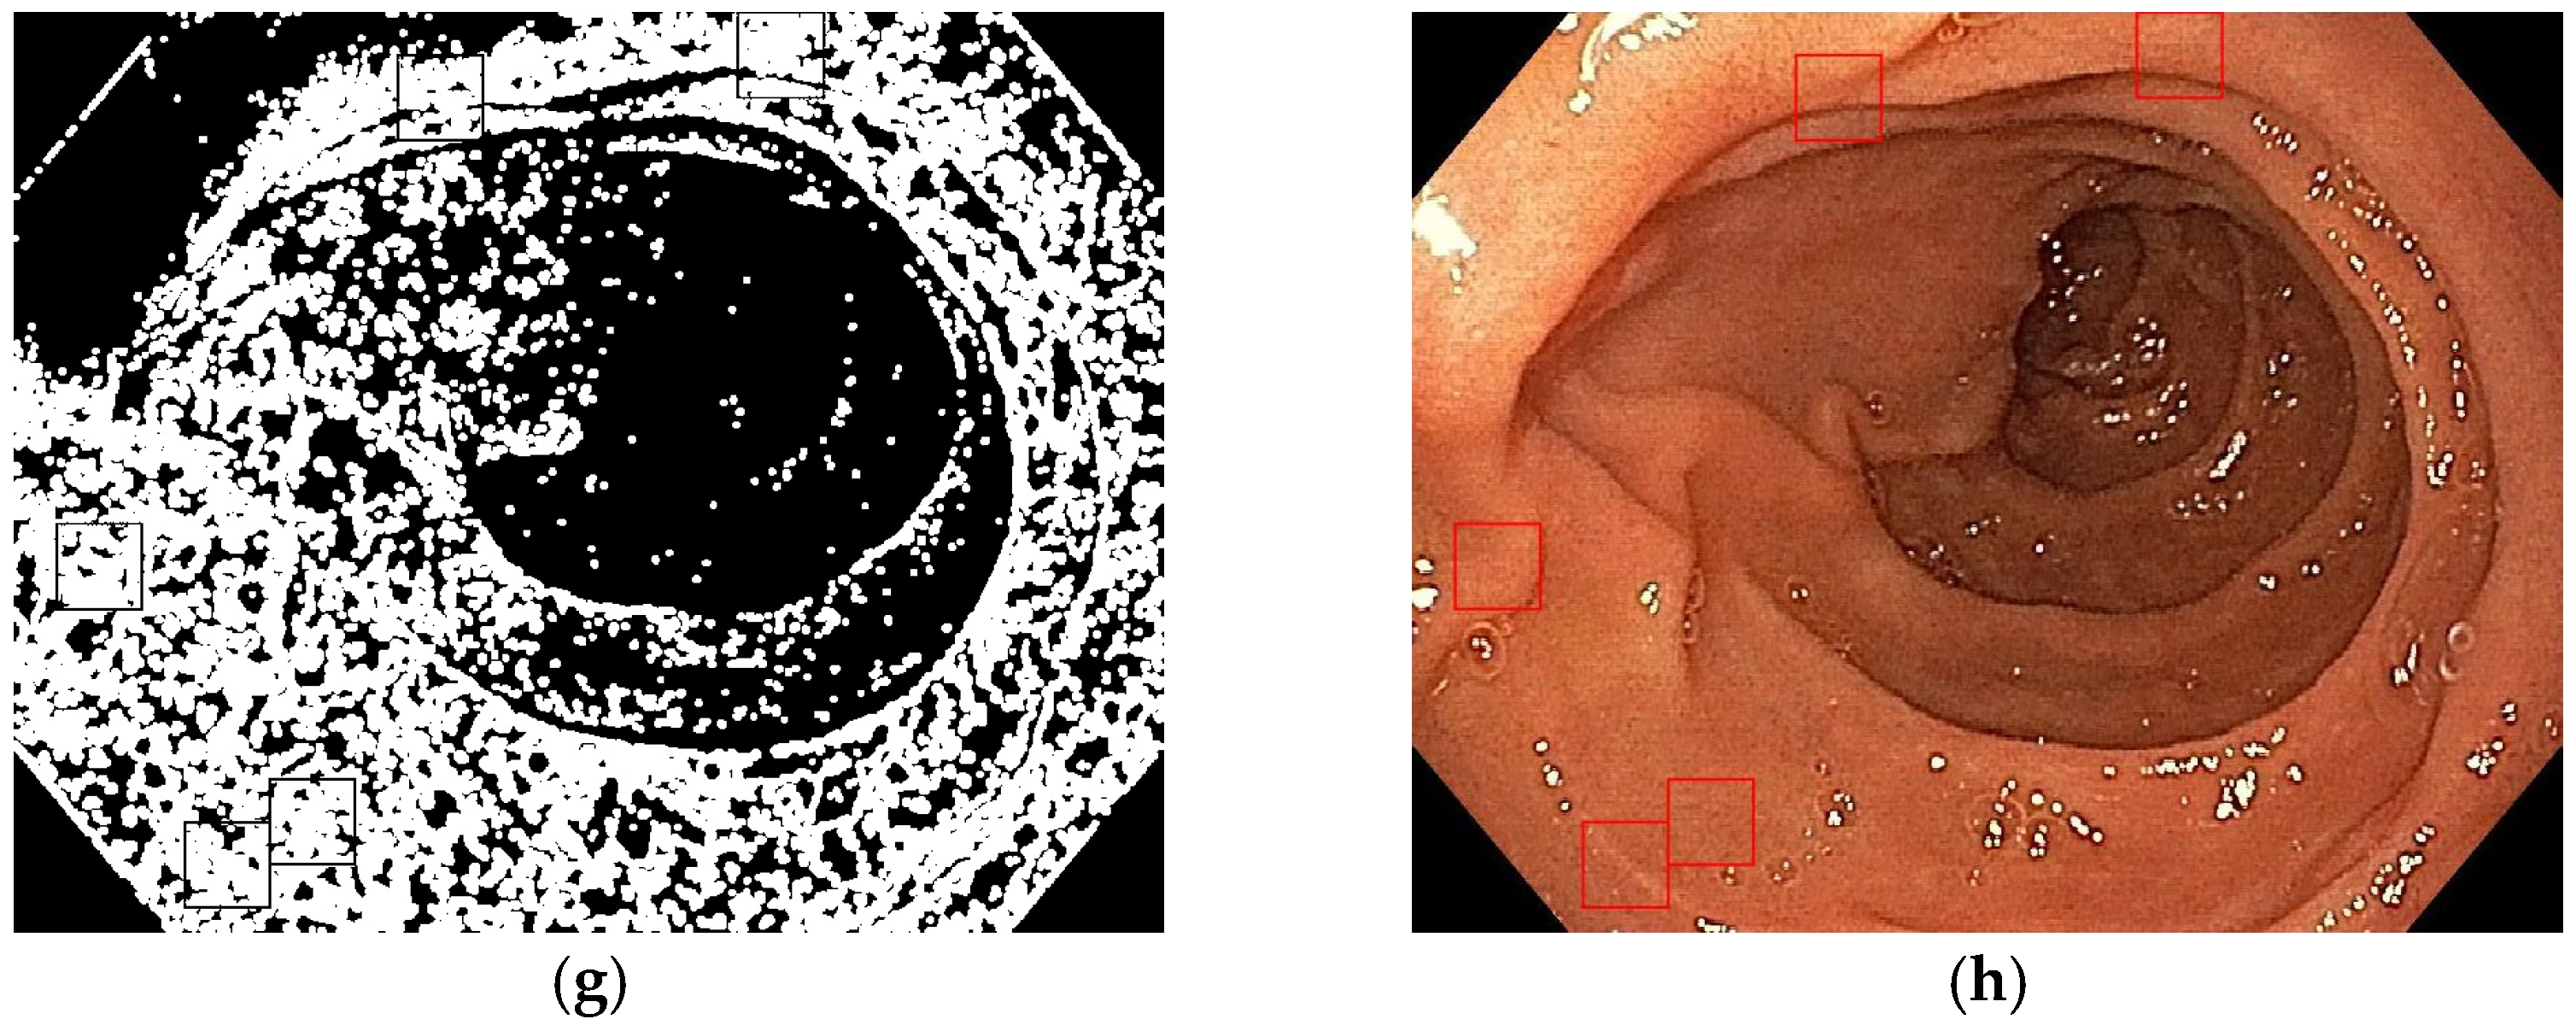

- Entropy filter applied on the gray level image;

- Binarization of the entropy-filtered image with high and low thresholds;

- Binarization of the gray level image using two high and low thresholds;

- Logic AND between binary images and dilatation;

- Patches selection according to the final binary image and the gray level range.